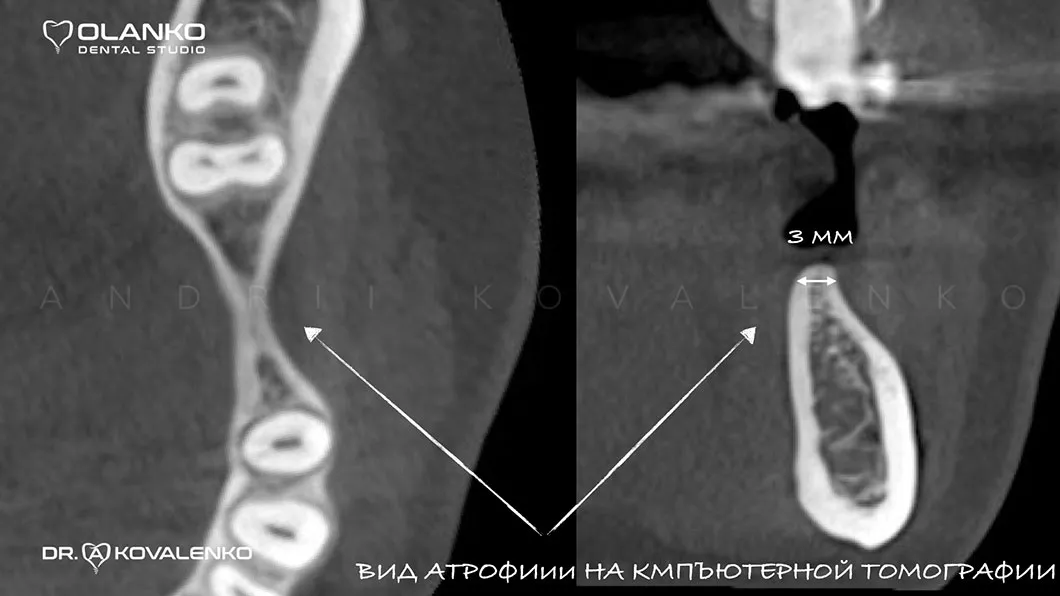

Атрофія - це прогресуюче зменшення кісткової тканини, що супроводжується також і зменшенням ширини та висоти альвеолярного гребеня. Розвивається після видалення зуба і є найпоширенішою перешкодою для встановлення зубного імплантату.

Спеціалісти Olanko dental studio (Оланко) м. Бровари, при виборі методу кісткової пластики, проводять детальний аналіз комп'ютерної томографії та віртуально розставляють положення майбутніх імплантатів в спеціальному програмному забезпеченні IMPLANT STUDIO 3Shape.

Вигляд щелепної кістки на 3D знімку до операції нарощування кістки